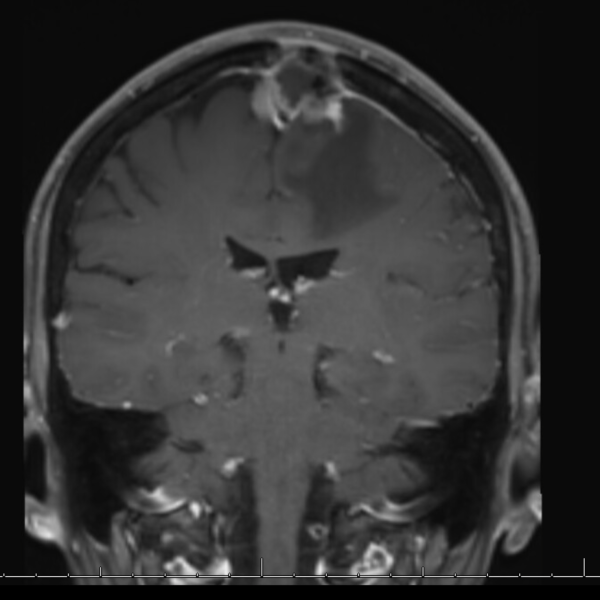

A 52 yo lady has a progression of residual disease after partial resection 5 months ago of a grade II meningioma of the falx. Unfortunately, at that time the patient did not accept treatment.

I would propose irradiating with FSRT the whole cavity and boosting with SRT the macroscopic disease. Would you share this opinion?

If not, and I suspect as much, given 5 months time to progression, then I would take the GTV and the surgical bed plus a 3 mm margin into brain tissue as CTV60/PTV60 (60 Gy in 30) then boost GTV residual +PTV with 6 Gy in 3 frx or 10 Gy in 5 frx depending what your comfortable with. Our data that will be presented and in submission suggests 66 in 33 or 70 Gy in 35 to result in better long term outcomes when residual vs 60 Gy in 30. I do sequential boost but you could SIB also. When volumes of residual are large I SIB otherwise I do the boost sequentially and a week or two gap using the Gamma Knife Icon. I would not single frx boost but fractionate the boost.